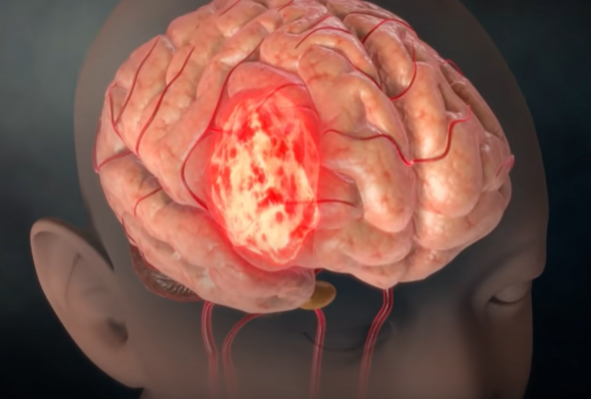

3. 그리고 뇌종양의 흔한 증상 역시 두통이다.

혈관 기형이 있다거나 혈전이 생겨서 혈관이 부풀어 오른다든지, 특히 정맥에 혈전이 생기면 두통이 심하게 나타날 수 있고, 또 하나는 머리 안쪽에 염증이 생기는 경우로서 뇌막염, 수막염, 뇌염, 결핵성 내막염이 있다. 또는 뇌압이 너무 올라가거나 떨어지면 심한 두통이 올 수 있다. 뇌압을 올리는 것은 뇌종양이 있다. 뇌에는 물이 있어 물을 만들어 내는 것이 너무 과다하거나 하루 3번 순환해야 하는데 물의 순환 과정이 막혀 물이 빠져나가지 못하는 경우에는 수두증이 생긴다.